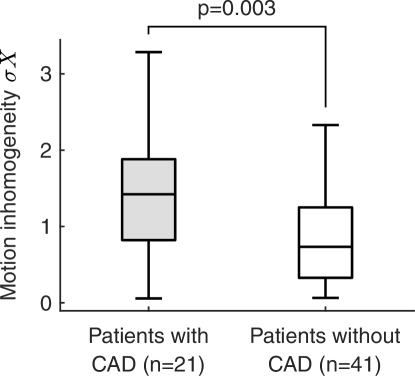

The association between either the motion inhomogeneity index or the peak-to-peak amplitude and participants characteristics is provided in Table 4. The strongest correlates to were coronary artery disease (, , Figure 8) and systolic blood pressure (, ). Interestingly, the association with coronary artery disease remained nearly-significant (, ) in a multivariable model after adjusting for systolic blood pressure and peak systolic value, the second and third strongest independent correlates. The peak-to-peak amplitude was strongly correlated with peripheral artery disease (, ) and hypertension (, ). These results are in accordance with previous findings showing that is associated with cardiovascular risk factors zahnd2012longitudinal . A significant association was also observed between and (, ). A qualitative analysis of the motion field in all participants did not reveal an association between motion homogeneity and putative local tissue stiffness (e.g. healthy sections or atherosclerotic plaques, Figure 7).

Let us start by briefly recalling the three hypotheses that were investigated in the present study. First, tracking of a single point is more prone to generate erroneous trajectories compared to exploiting the collaboration of multiple points. The increased robustness of DBM was demonstrated in Section III.2 against a state-of-the-art method based on single-point tracking, with an average absolute error of compared to . Second, the selection of a single point is an analyst-dependent procedure and may hinder the reliability of results exploitation. The impact caused by single-point selection when measuring the peak-to-peak motion amplitude was assessed in Section III.3, and showed that the intra-participant variability was . Although relatively reduced compared to the total magnitude of the motion, this additional source of error can be avoided with a global analysis. Third, motion trajectories resulting from a single point do not allow the analysis of the displacement field (in)homogeneity across the entire length of the artery, which may reflect cardiovascular health. The results presented in Section III.4 establish that the LOKI-derived inhomogeneity index is strongly associated with coronary heart disease (, , Figure 8).

Although the motion inhomogeneity index is amplitude-independent since it is derived from the normalized motion field, this index was correlated to the peak-to-peak amplitude (, ). Nevertheless, confronting those parameters to the participants characteristics indicated that and are strongly correlated to different predictor variables (Table 4). These preliminary findings suggest that do not simply replicate the information already captured by but instead represents a complementary measure of cardiovascular risk. A comprehensive analysis of the association of motion-derived parameters with risk factors was beyond the scope of the present study. Future work involving a greater number of participants will be conducted to confirm the clinical usefulness of analyzing the spatial inhomogeneity of the motion along the wall to characterize at-risk individuals.